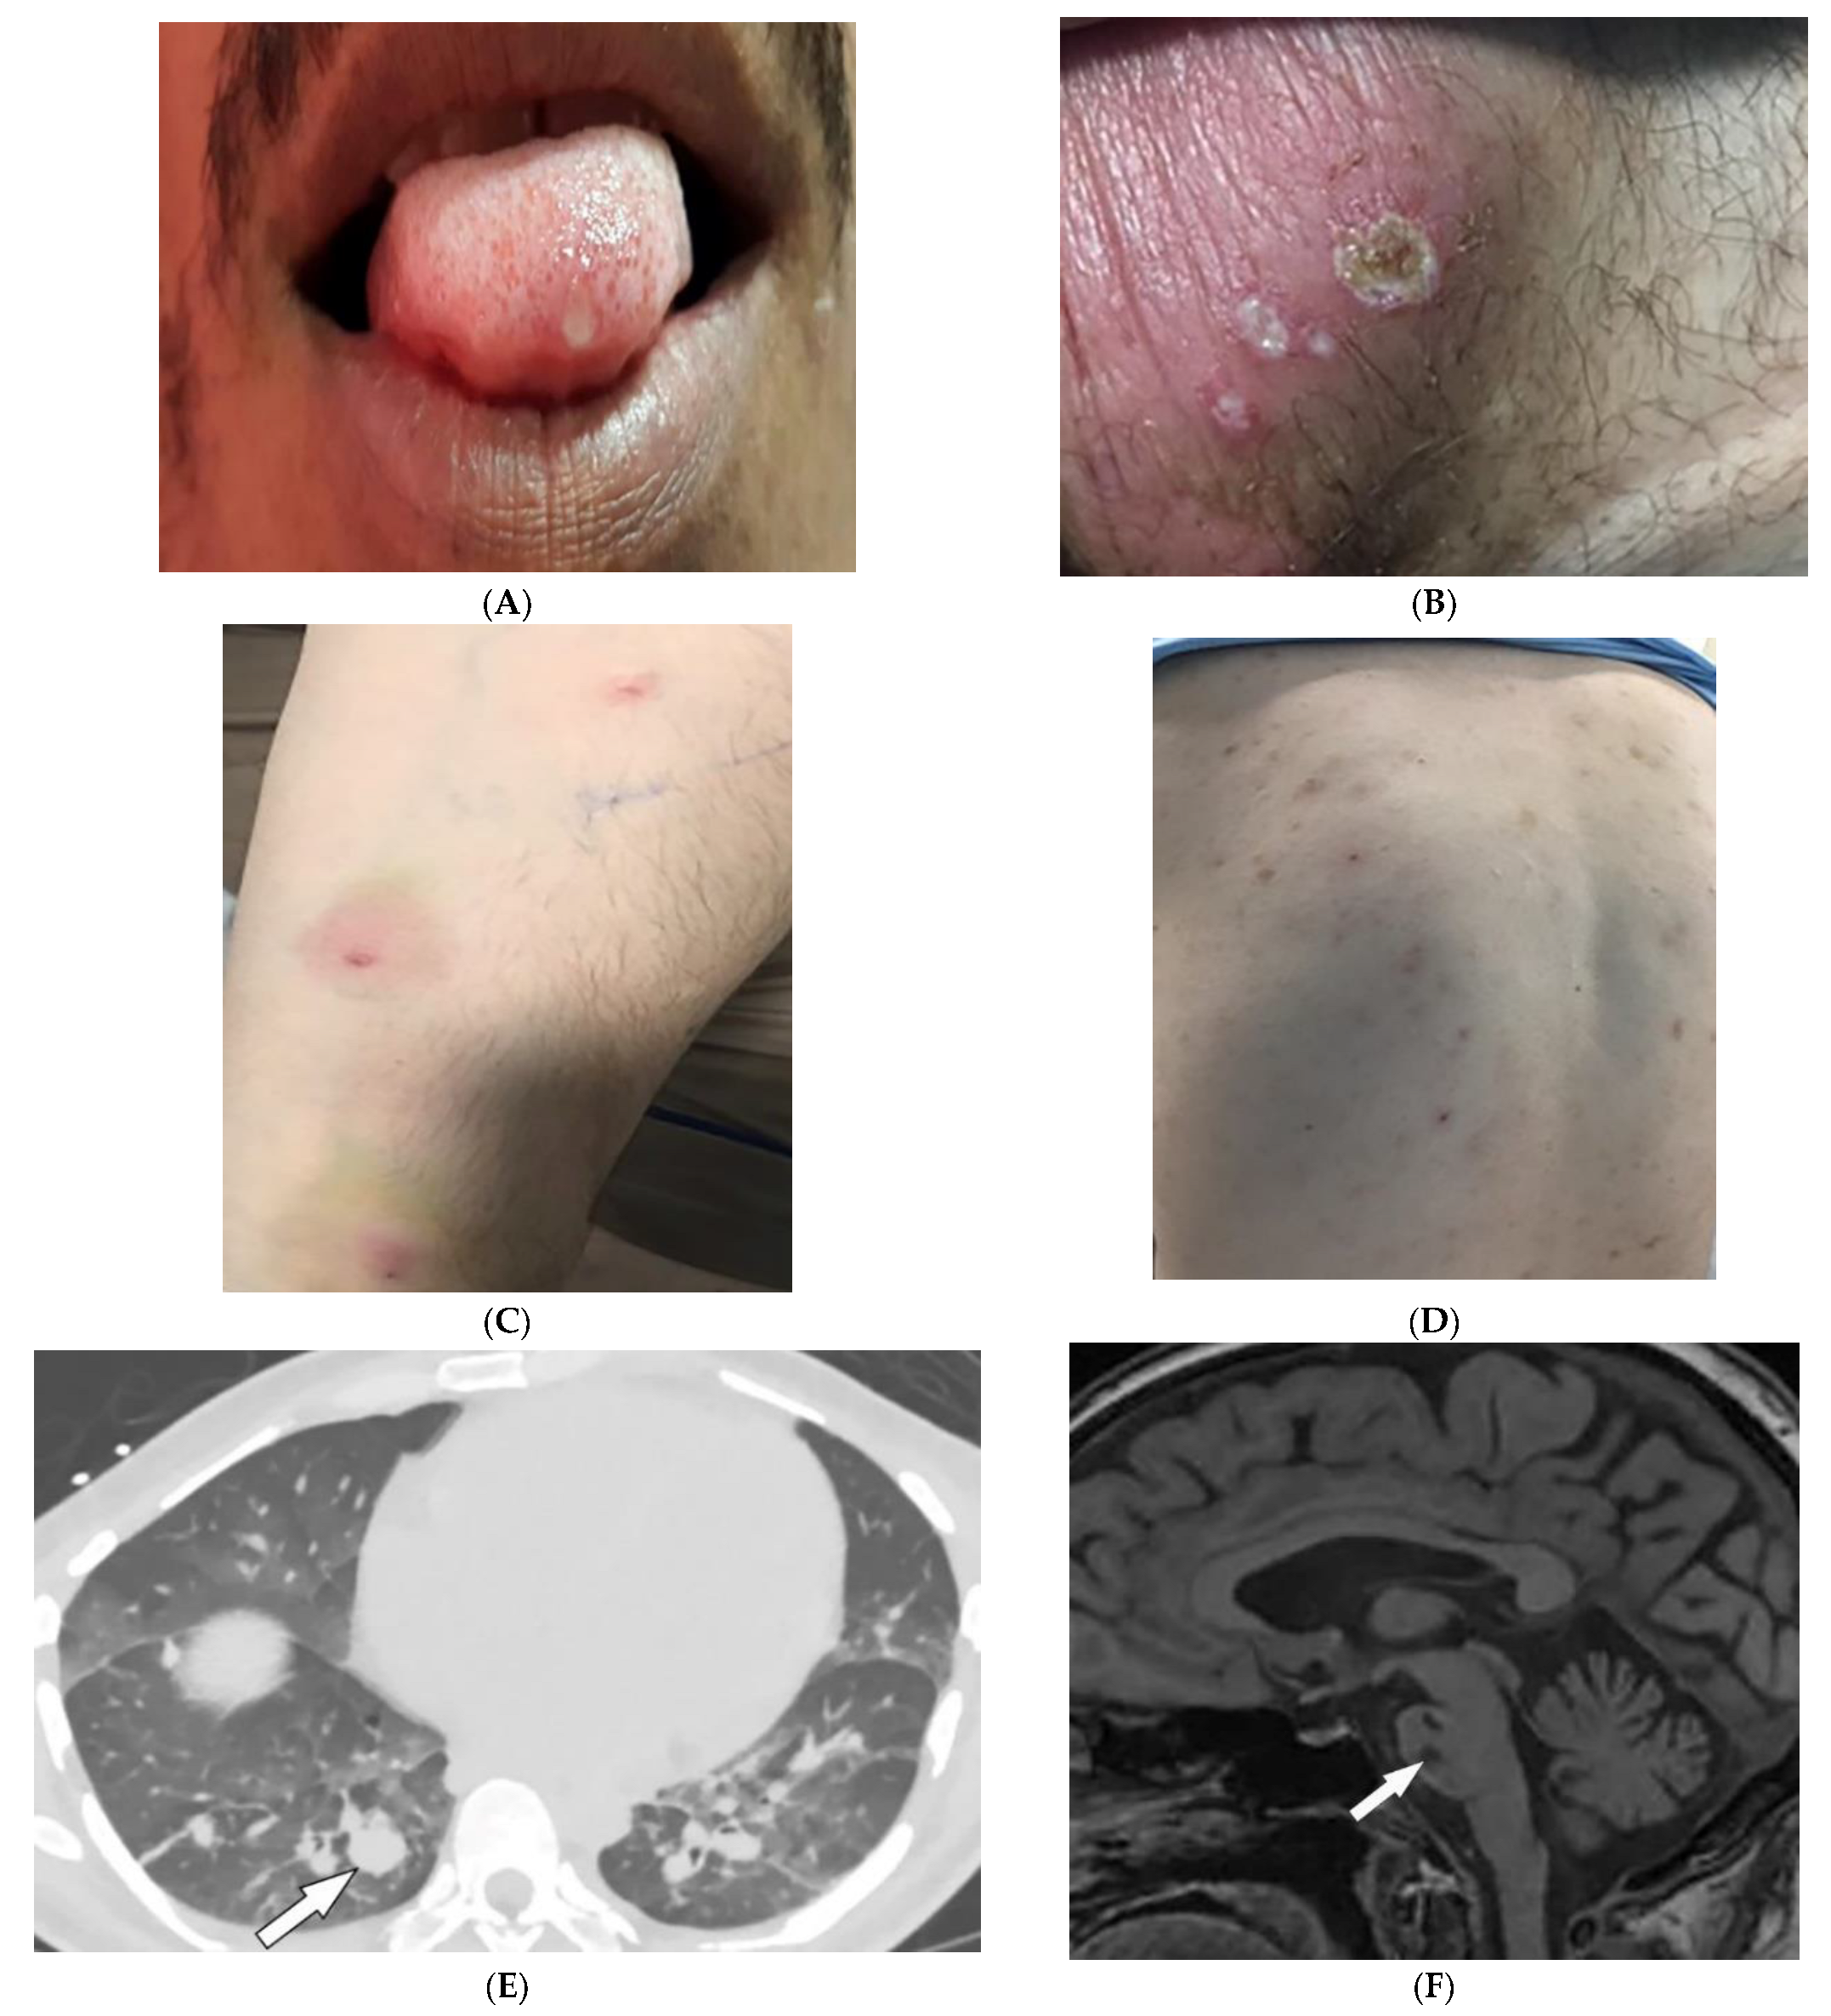

3.11. Buschke–Ollendorff Syndrome

| Buschke–Ollendorff syndrome | Dermatofibrosis lenticularis disseminata Osteopoikilosis Melorheostosis | Bony islands and multiple sclerotic lesions cause mottled appearance Cortical thickening with undulating bone |